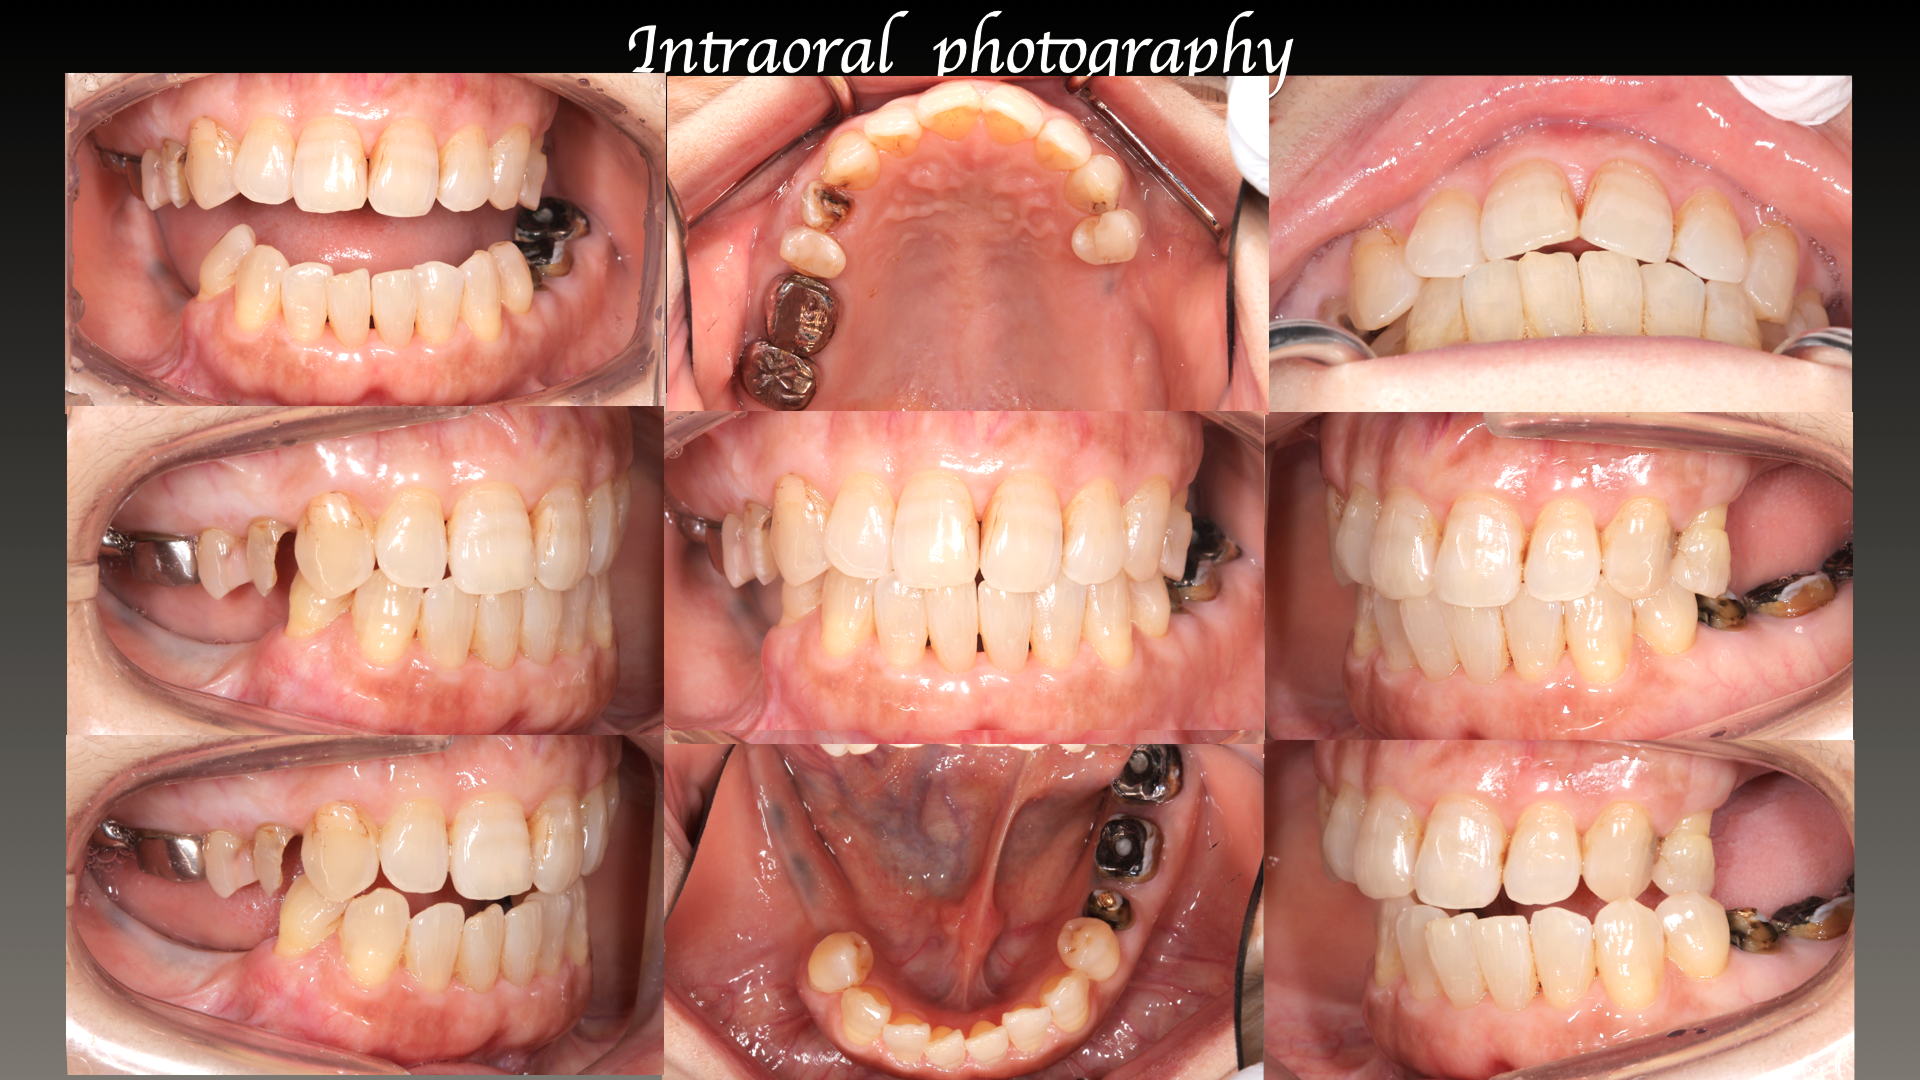

主訴:左下の歯が外れた。

治療概要:左下の歯が外れたことがきっかけで来院されました。右下と左上には歯がない状態でした。

治療前

治療後

生理的咬合と判断に至った背景

外れた左下の歯ですが、歯茎から出ている歯の部分が明らかに短く、この状態で被せ直しをしても維持力がないためすぐに外れてしまう事が予想されました。

また、奥歯がないためこの歯には噛む時の力が過剰にかかってしまいます。

この方の場合右の歯も少なく、主訴である左下の歯だけ治療をしたとしても今残っている歯も含めてどんどん悪くなることが予想されました。

このような理由で口腔全体を含めた「全顎の治療」計画を提案させていただきました。

現状残っている歯の状態から、この患者さまは「生理的咬合」であると診断し、現状噛んでいる歯の位置の修正とは行わずに、歯がないところ、歯が欠けているところを治すだけで安定すると考え治療を行っています。